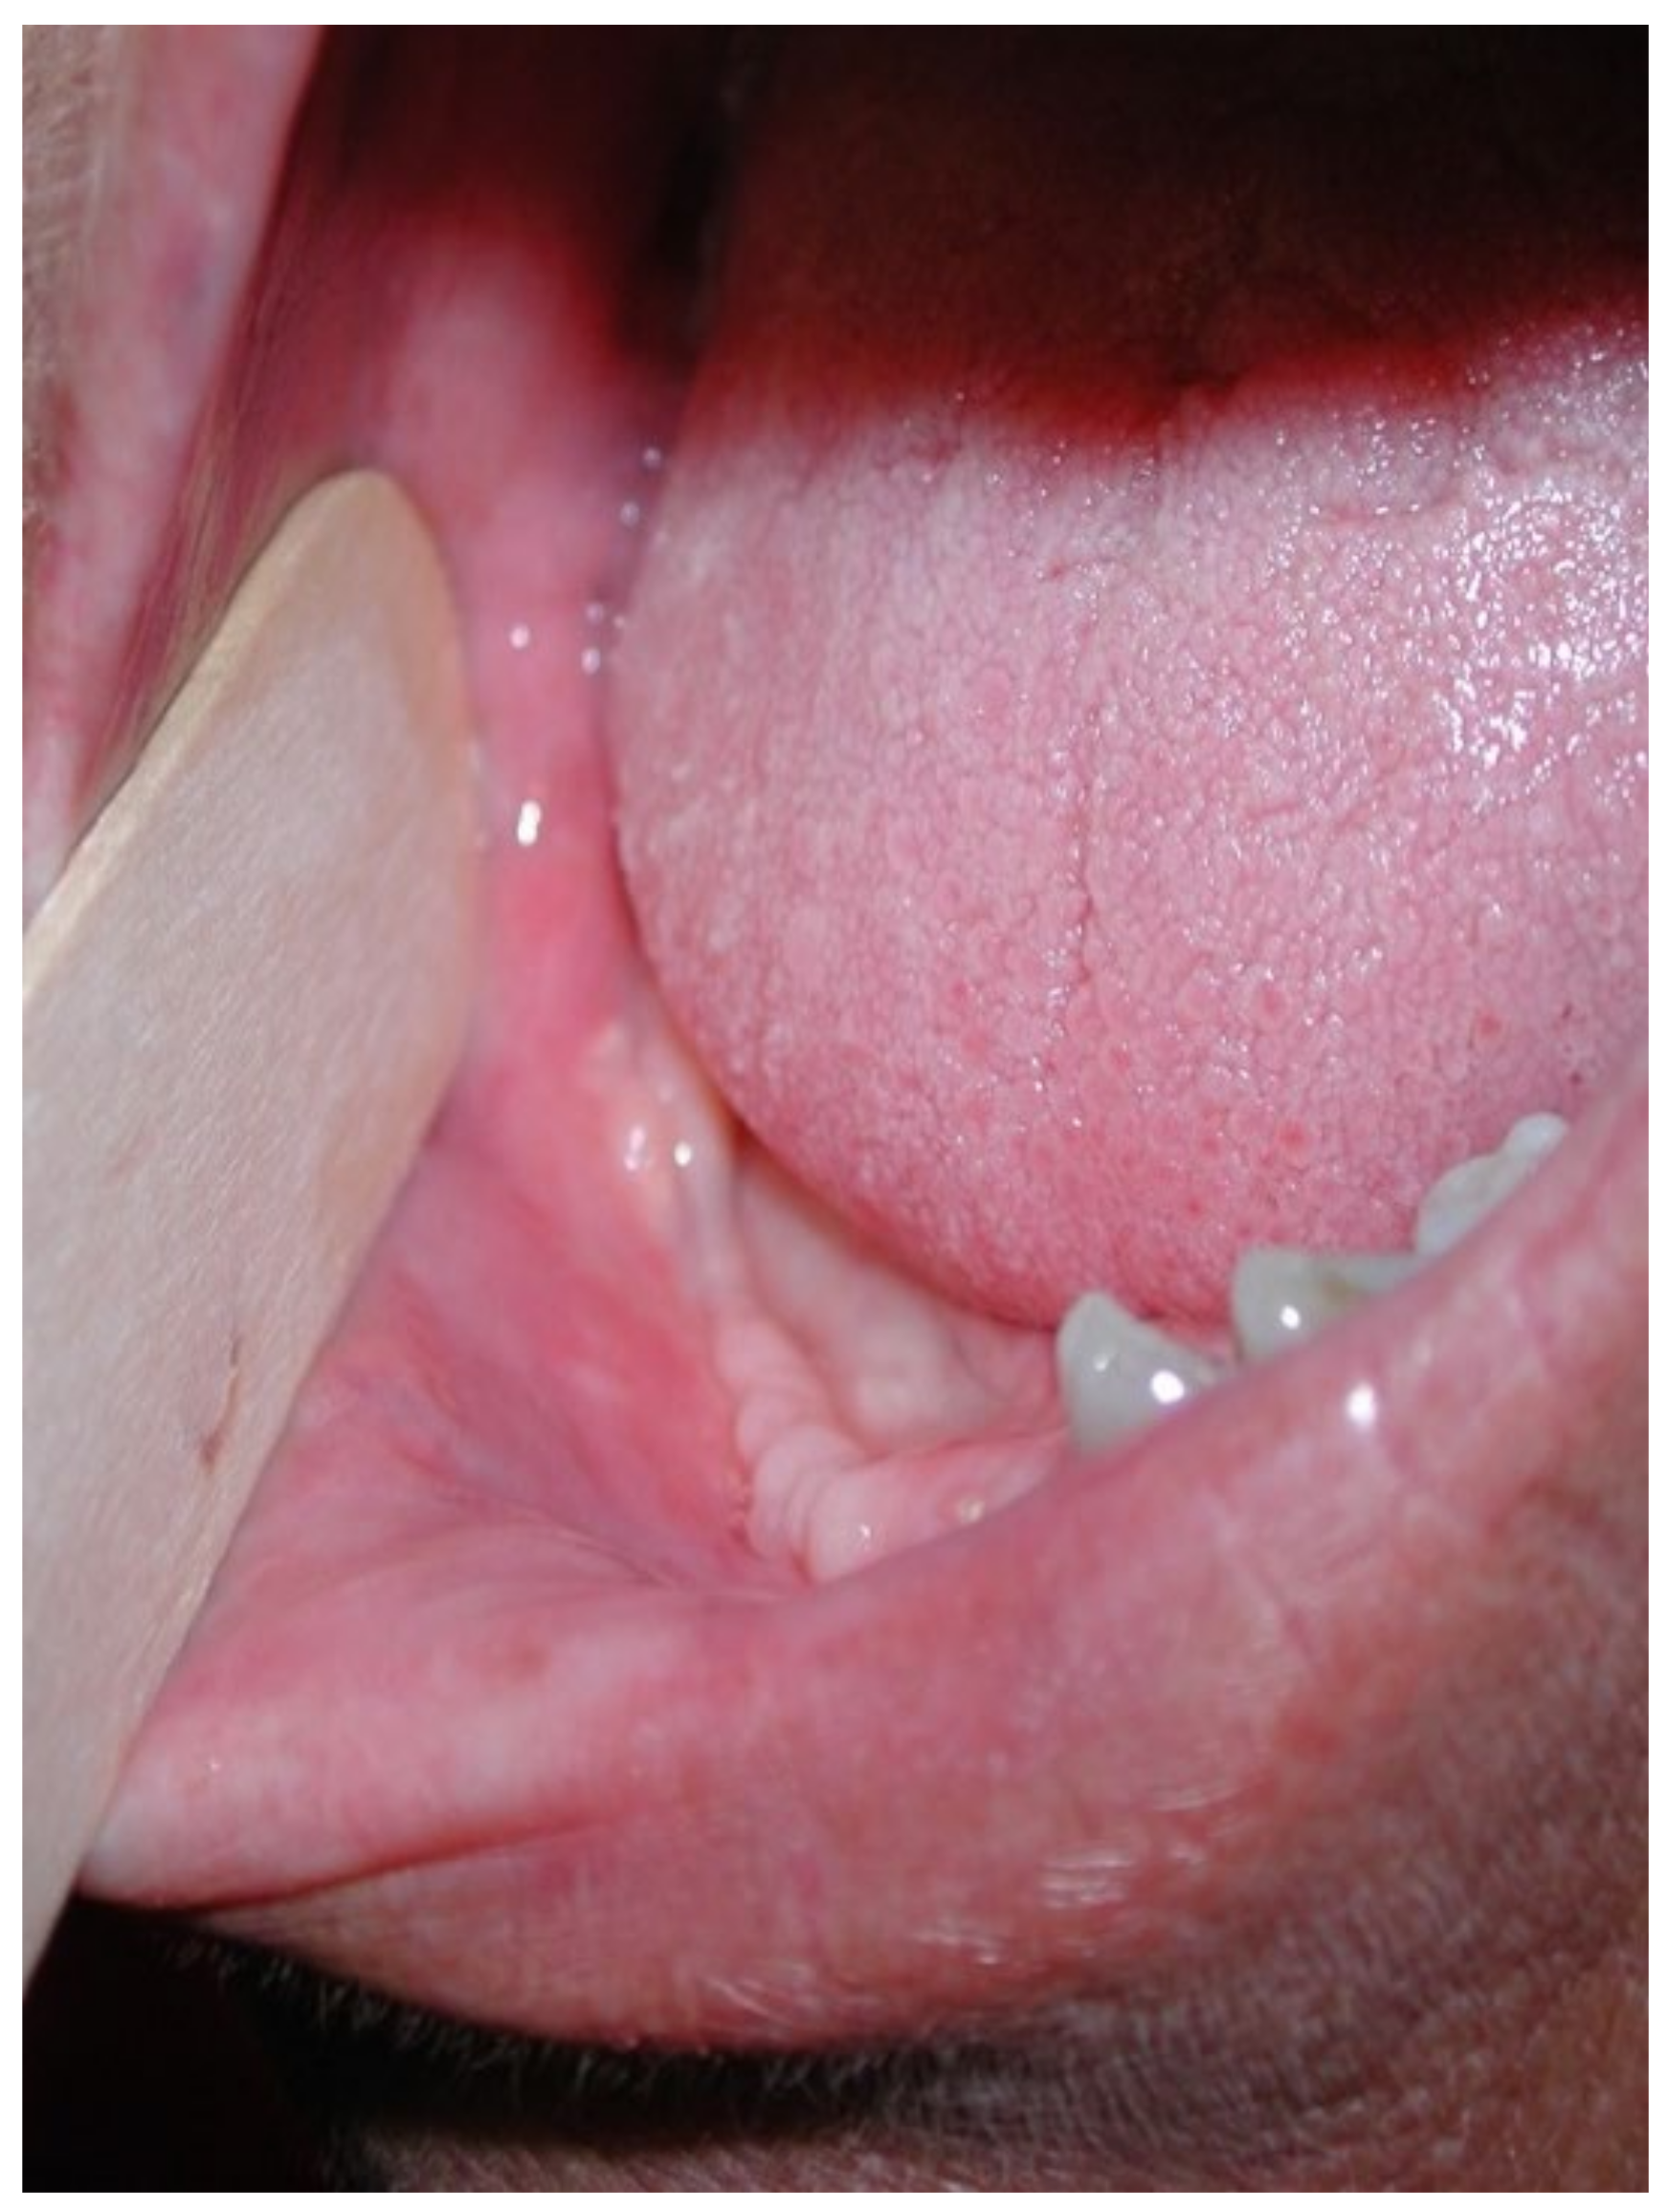

3.1. Clinical Case 1

3.2. Clinical Case 2

3.3. Clinical Case 3

3.4. Clinical Case 4

3.5. Clinical Case 5

3.6. Clinical Case 6